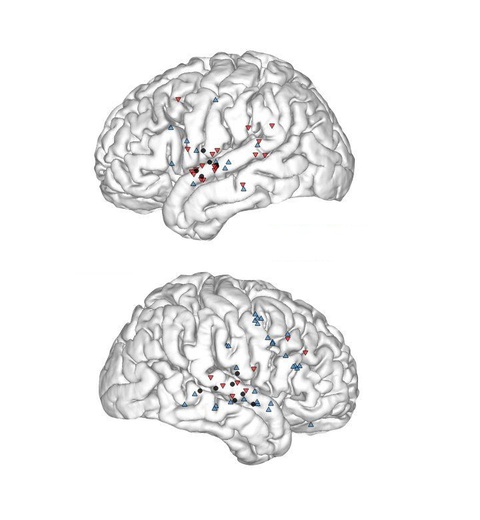

Xem xét các tín hiệu vỏ não, nhóm nghiên cứu nhận thấy có những khu vực tế bào thần kinh hào hứng tiếp nhận thông tin mới khi học ngôn ngữ, trái lại một số vùng hầu như không có động tĩnh gì. Mức độ đối lập của hai trạng thái càng ít, khả năng nhanh nhạy trong các bài tập thí nghiệm càng cao.

Màu xanh là những vùng "hào hứng" với những thông tin ngoại ngữ mới, trái với sự tĩnh lặng của vùng đỏ - Ảnh: Susan Merrell